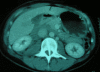

Case presentation: In this case report we present the unique, as far as the literature is concerned, unprovoked woman's injury to the abdomen by a swordfish. There are only four cases of swordfish attacks on humans in the literature - one resulted to thoracic trauma, two to head trauma and one to knee trauma, one of which was fatal - none of which were unprovoked. Three victims were professional or amateur fishermen whereas in the last reported case the victim was a bather as in our case. Our case is the only case where organic debris of animal's origin remained in the spinal canal after penetrating trauma.